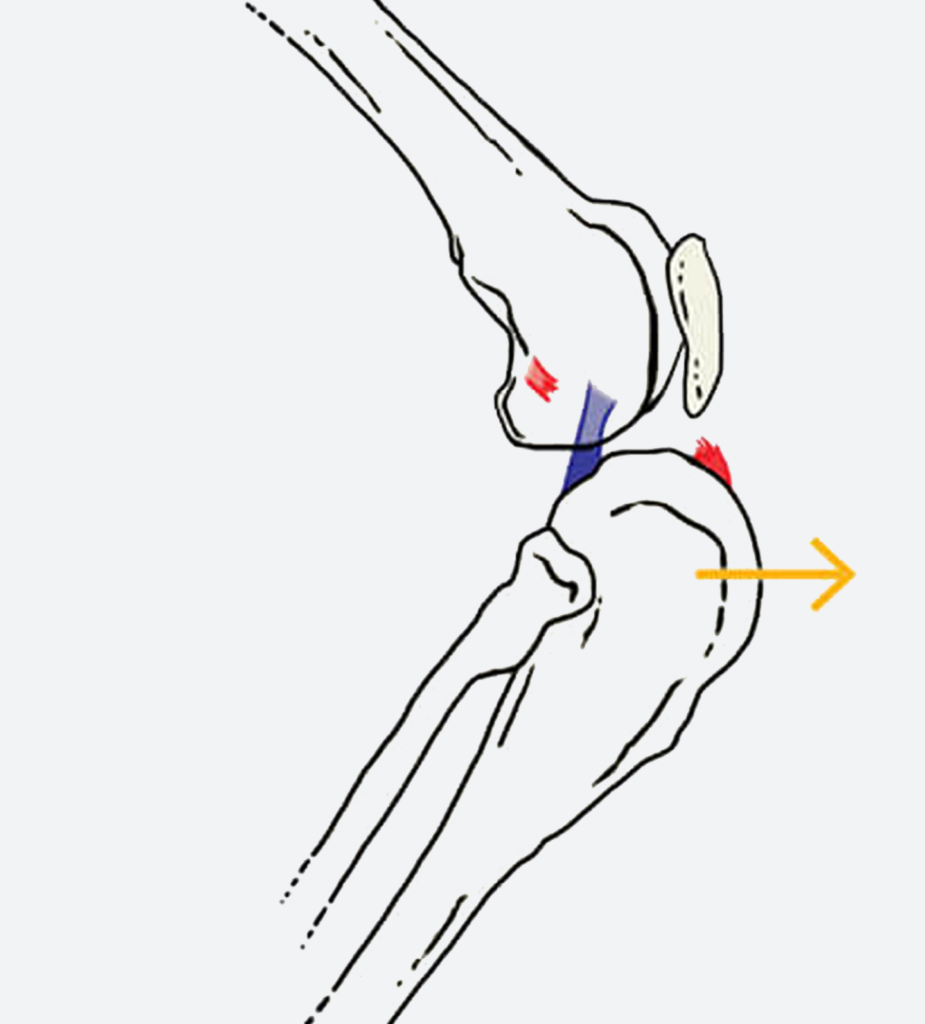

- Với chứng trật xương bánh chè: Trong trường hợp bình thường, xương bánh chè phải nằm chính giữa rãnh trên xương đùi để khớp vận hành trơn tru, nhưng ở Bông Lúa, xương bánh chè đã trượt hoàn toàn ra khỏi rãnh và bị khóa cứng ở vị trí sai, khiến bé không thể duỗi thẳng chân và chỉ có thể di chuyển bằng ba chân còn lại.

- Với chấn thương đứt dây chằng: Dây chằng chéo trước có vai trò như một dây neo quan trọng, giữ cho xương chày và xương đùi liên kết chặt chẽ với nhau – khi dây chằng này đứt, xương chày mất sự kiềm chế và trượt về phía trước mỗi khi chịu lực, khiến hai khúc xương không còn khớp đúng trục và toàn bộ khớp gối mất ổn định hoàn toàn.

- Phẫu thuật TPLO (Tibial Plateau Leveling Osteotomy): Đồng thời áp dụng phẫu thuật TPLO để ổn định khớp gối lâu dài. Điểm đặc biệt của TPLO là thay vì nối dây chằng nhân tạo dễ đứt lại, kỹ thuật này thay đổi góc nghiêng của xương để khớp gối tự ổn định vững chắc ngay cả khi dây chằng đã mất chức năng.